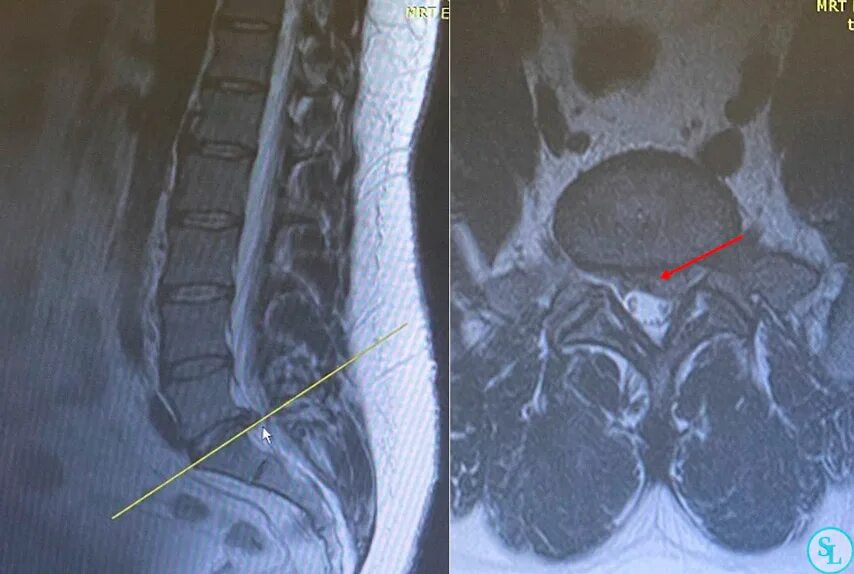

Операция удаление грыжи l5 s1